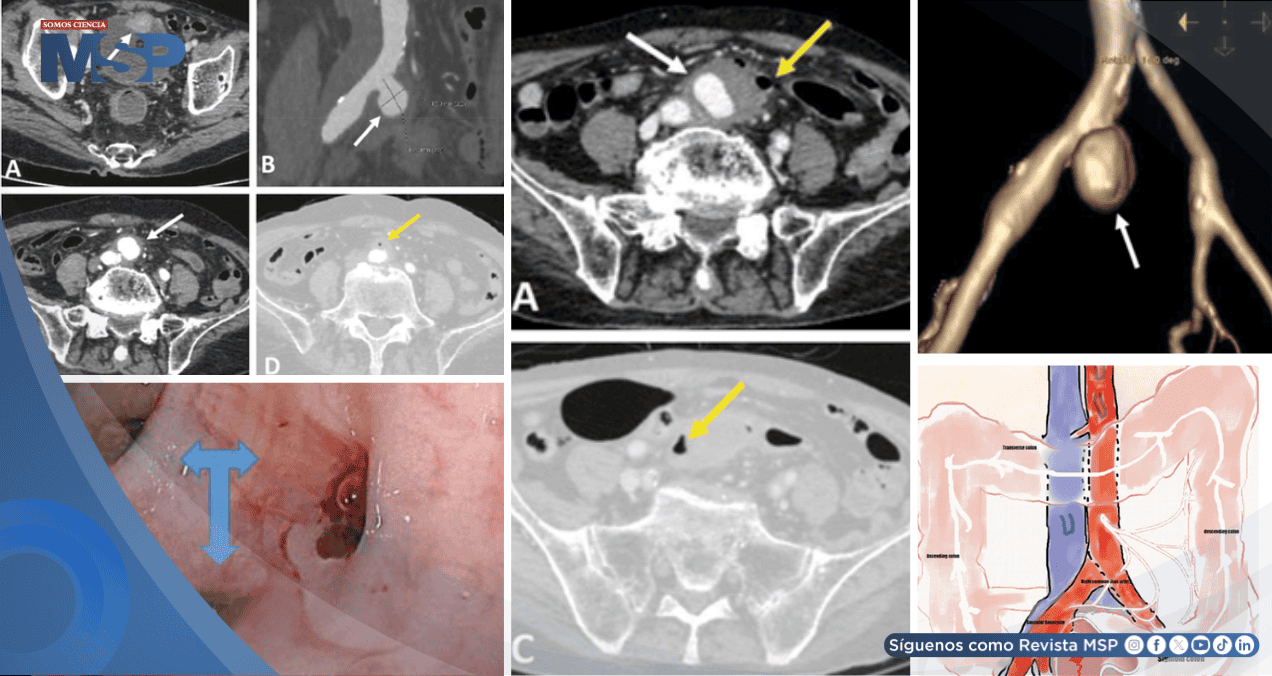

La tomografía computarizada identificó el crecimiento acelerado del aneurisma, gas perivascular e inflamación severa, hallazgos que permitieron diagnosticar una rara fístula entre la arteria ilíaca y el colon.

La situación clínica había empeorado considerablemente. Una nueva tomografía computarizada abdominal de urgencia mostró un cambio dramático: el aneurisma ilíaco había crecido de forma notable, alcanzando un tamaño de 31x36x40 milímetros, y ahora presentaba un trombo mural de 15 milímetros de espesor.

Los signos de inflamación y la presencia de gas en los tejidos circundantes también se habían incrementado de manera marcada.

El hallazgo radiológico más crítico fue la evidente adhesión de la pared anterior del aneurisma a la pared posterior del colon sigmoide. Para confirmar la sospecha, se realizó una colonoscopia, la cual mostró sangre fresca activa en esa misma zona del colon.

Con estas pruebas, se estableció el diagnóstico definitivo: una fístula aneurisma-colónica, una comunicación patológica entre el aneurisma infectado, denominado micótico, de la arteria ilíaca común derecha y la luz del colon sigmoide.

Sus hallazgos son determinantes: muestra el crecimiento del aneurisma, signos de infección activa como el edema y el gas en la grasa perivascular, y, de manera crítica, la relación anatómica entre el aneurisma y las estructuras digestivas adyacentes, sugiriendo la fístula. La presencia de gas extraintestinal o la extravasación de medio de contraste hacia la luz del colon son hallazgos altamente específicos.